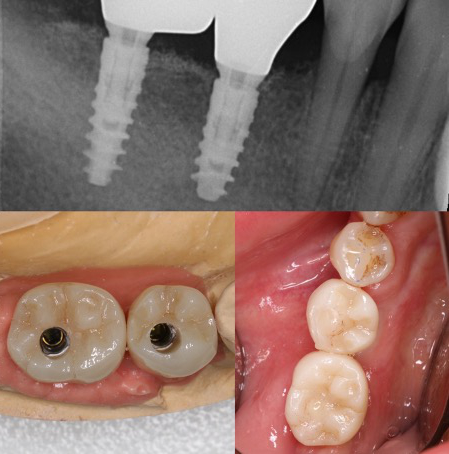

En effet, une reconstruction osseuse (Greffe osseuse) est indispensable, pour rétablir la hauteur ou la largeur de l’os maxillaire, avant ou en même temps que l’implantation. Ce sont soit les os du patient ou un substitut osseux qui sont utilisés comme matériau de comblement.

Les études nous montrent des résultats extraordinaires avec l’utilisation exclusive ou mélangée que ce soit avec de l’os synthétique ou de l’os autologue (os prélevé dans la bouche du patient pendant l’intervention de reconstruction osseuse).

Il y a plusieurs techniques des reconstructions osseuses et une planification correcte nous donne la possibilité de choisir la technique la plus appropriée pour chaque situation.